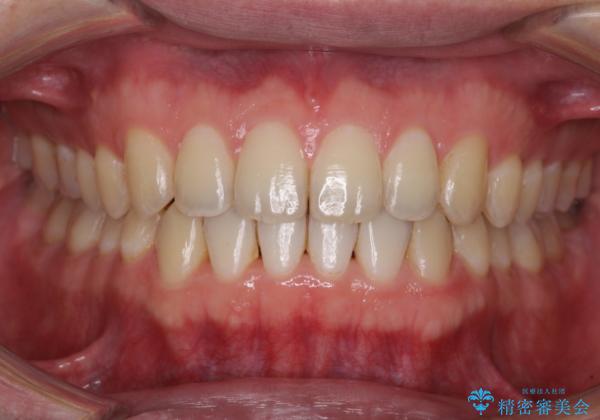

インビザラインにより、上下の歯列を側方に拡大しつつ、前歯の隙間を閉じていくこととしました。

1日22時間の装着時間をしっかりと守ってくださったので、隙間がきれいに閉じ、口元の突出感も改善することができました。